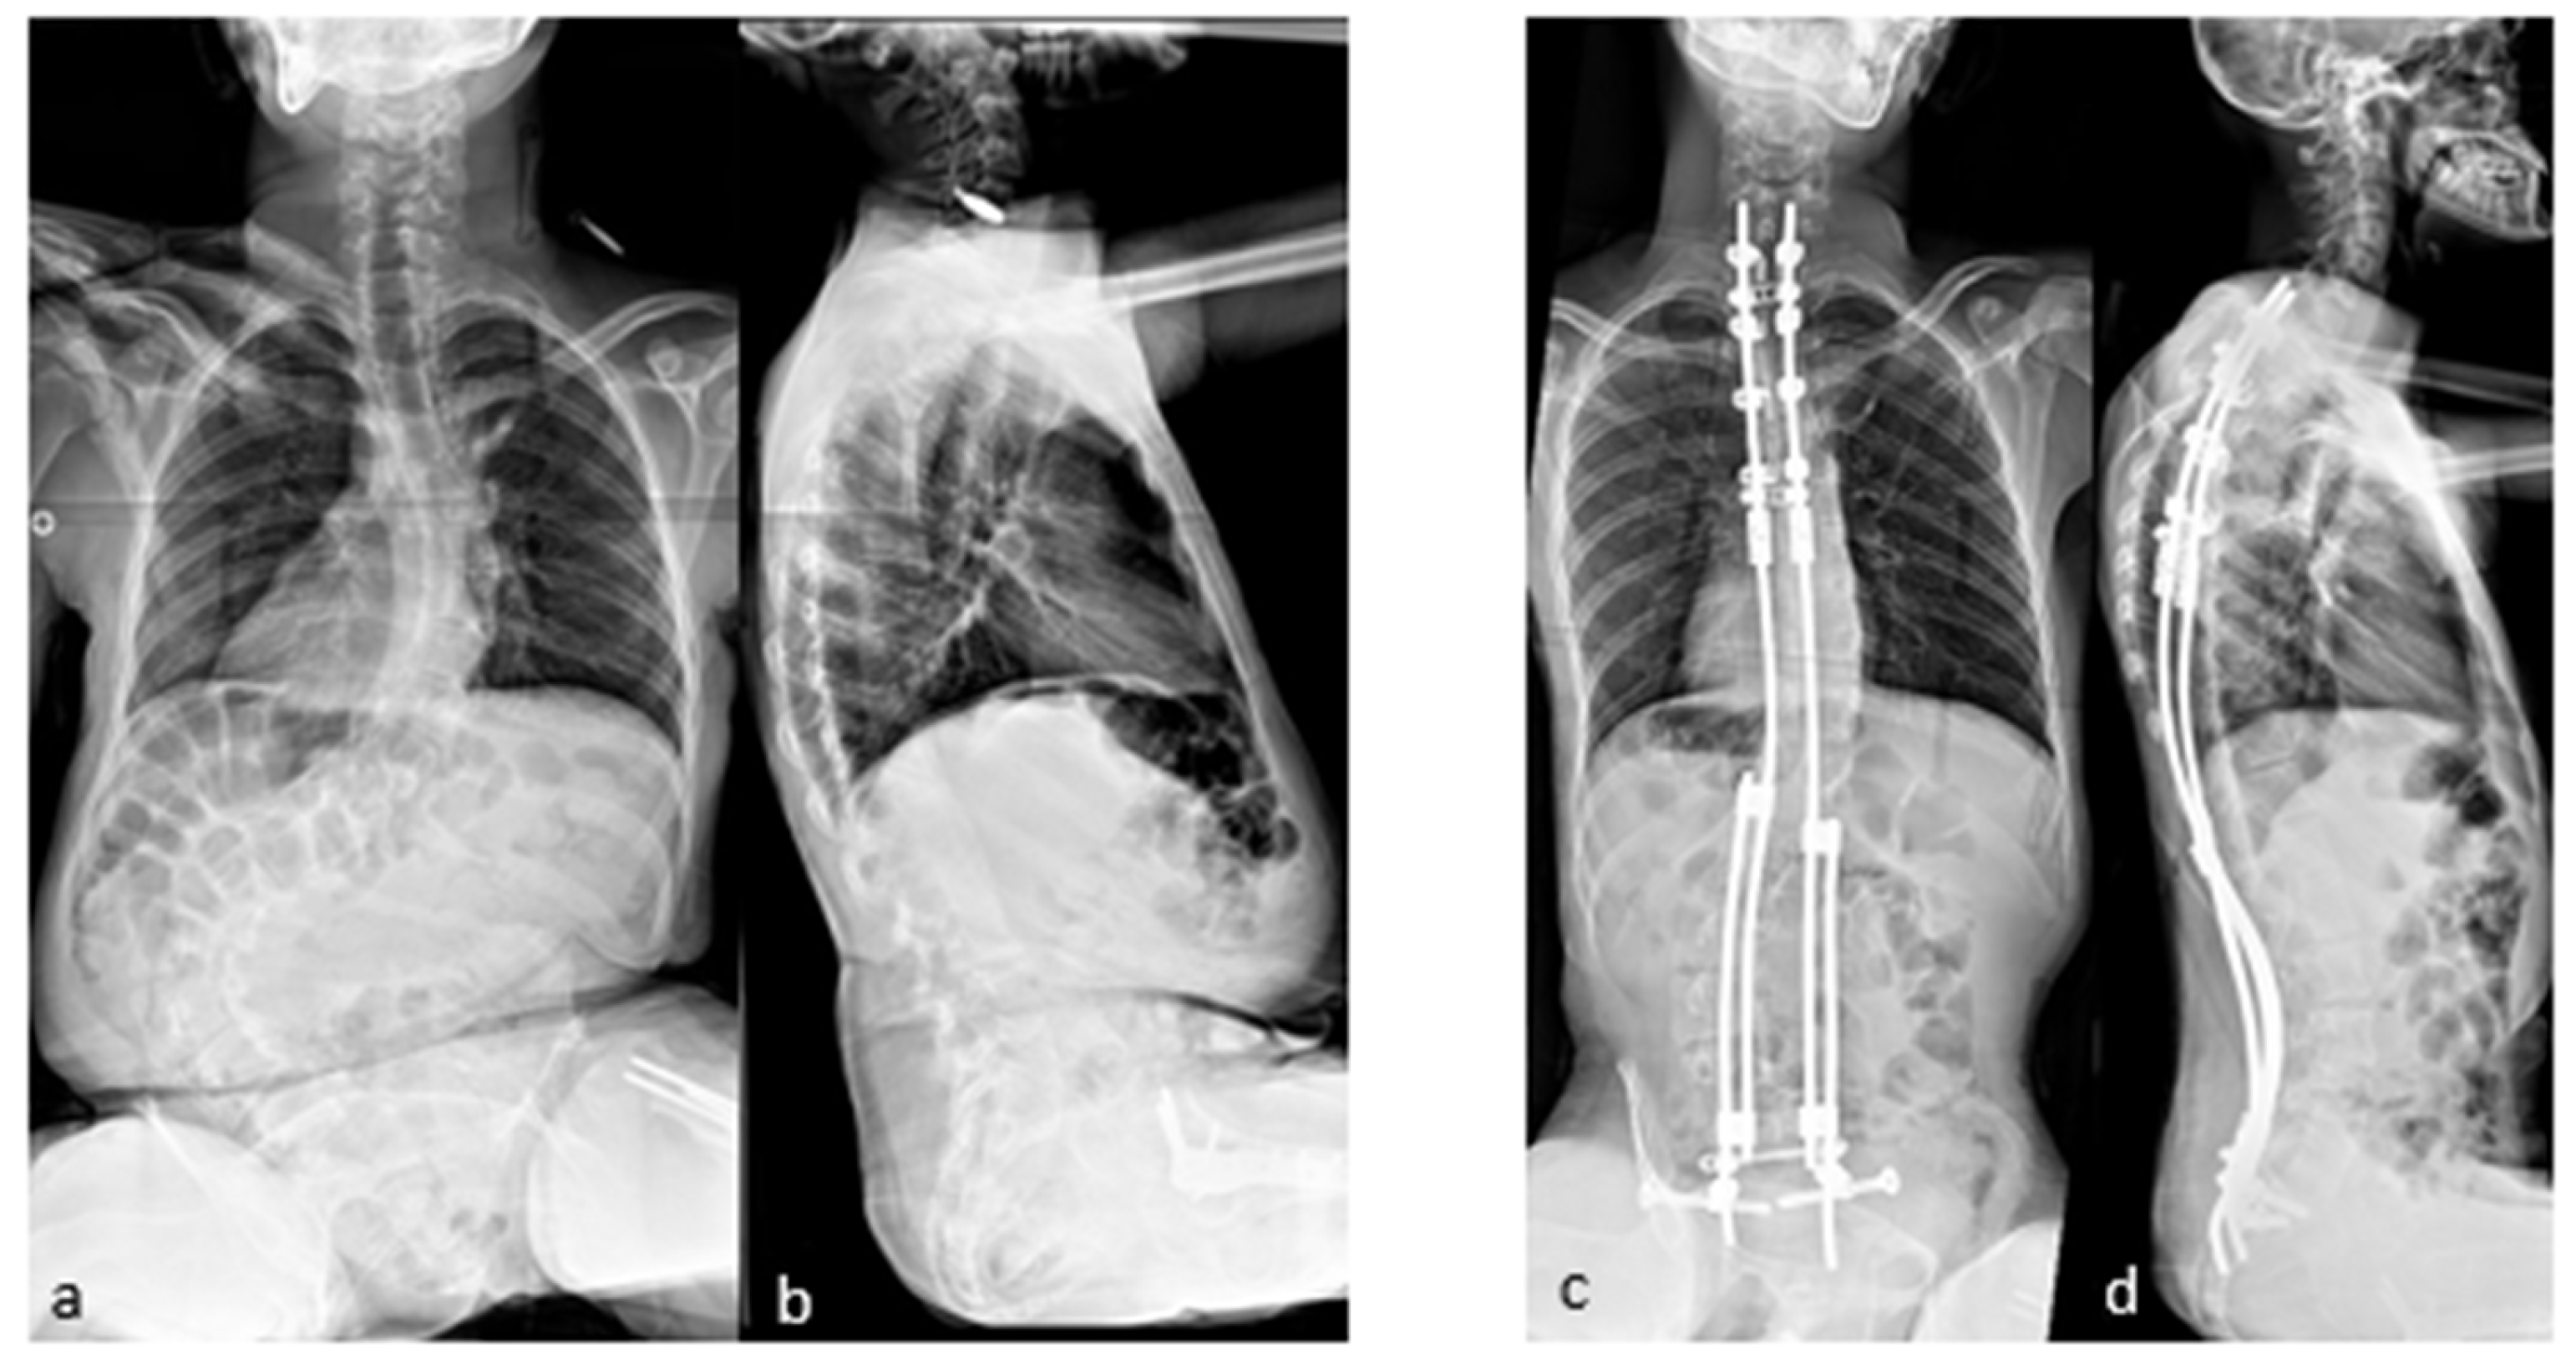

If necessary, additional rod lengthening can be performed one–two years after the initial surgery to correct the residual curve or pelvic obliquity, or to accommodate growth in a young skeletally immature patient (Figure 4).

A series of the first 100 patients with neuromuscular scoliosis underwent MIBF at an average age of 11.5 years. The results were published in 2021, with a minimum follow up of 5 years [25]. The mean correction rates at the last follow up were 67% for spinal deformity and 83% for pelvic obliquity. This degree of correction of pelvic obliquity was achieved by an asymmetric additional rod-lengthening procedure, as shown in Figure 4. The overall complication rate in this series was 23%, of which 16% were infectious. The majority of cases were cerebral palsy, and five cases had spina bifida as the etiology. A total of five cases of rod fracture were reported in the first series. Vertebral arthrodesis was not performed for any patient in this study.

Figure 4. (a,b) Preoperative radiographs of a 12-year-old boy with cerebral palsy; (c,d) postoperative radiographs; (e,f) Radiographs after rod lengthening; (gj) initial and 6-year postoperative clinical pictures.